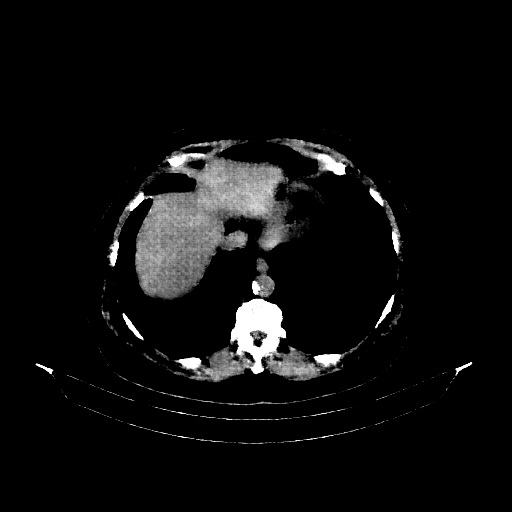

Original NATIVE CT scan (input)

Full window (WL 1023.5, WW 4095 β†’ Low βˆ’1024, High +3071)

Actual HU range: [-160.0, 240.0]

Lung window (WL -600, WW 1500 β†’ Low βˆ’1350, High +150)

Actual HU range: [-160.0, 150.0]

Mediastinum window (WL 40, WW 400 β†’ Low βˆ’160, High +240)